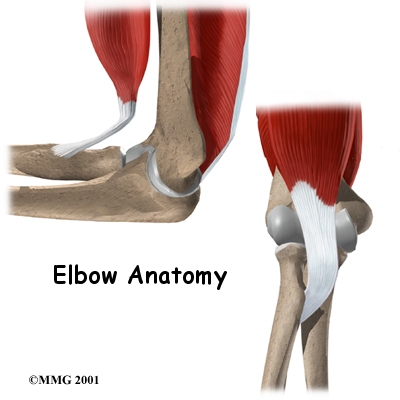

Ligaments and Tendons

There are several important ligaments in the elbow. Ligaments are soft tissue structures that connect bones to bones. The ligaments around a joint usually combine together to form a joint capsule. A joint capsule is a watertight sac that surrounds a joint and contains lubricating fluid called synovial fluid.

In the elbow, two of the most important ligaments are the medial collateral ligament and the lateral collateral ligament. The medial collateral is on the inside edge of the elbow, and the lateral collateral is on the outside edge. Together these two ligaments connect the humerus to the ulna and radius, and keep the bones tightly in place as they move around the end of the humerus. These ligaments are the main source of stability for the elbow but can be torn when there is an injury or dislocation to the elbow. If they do not heal correctly the elbow can be too loose, or unstable.

There is also an important ligament called the annular ligament that wraps around the radial head and holds it tight against the ulna. The word annular means ring shaped, and the annular ligament forms a ring around the radial head as it holds it in place. This ligament can be torn when the entire elbow or just the radial head is dislocated.

There are several important tendons around the elbow. The biceps tendon attaches the large biceps muscle on the front of the arm to the radius and allows the elbow to bend with force. You can feel this tendon crossing the front crease of the elbow when you tighten the biceps muscle. The triceps tendon connects the large triceps muscle on the back of the arm with the ulna. It allows the elbow to straighten with force, such as when you perform a push-up.

The muscles of the forearm cross the elbow and attach to the humerus. The outside, or lateral boney bump just above the elbow is called the lateral epicondyle. Most of the muscles that straighten the fingers and extend the wrist all come together in one tendon to attach in this area. The inside, or medial, boney bump just above the elbow is called the medial epicondyle. Most of the muscles that bend the fingers and wrist all come together in one tendon to attach in this area. These two tendons are important to understand because they are a common location of tendonitis such as golfer’s elbow (medial common flexor tendonitis) and tennis elbow (lateral common extensor tendonitis.)

Muscles

The main muscles that are important at the elbow have been mentioned above in the discussion about tendons. They are the biceps, the triceps, the wrist extensors (attaching to the lateral epicondyle) and the wrist flexors (attaching to the medial epicondyle).